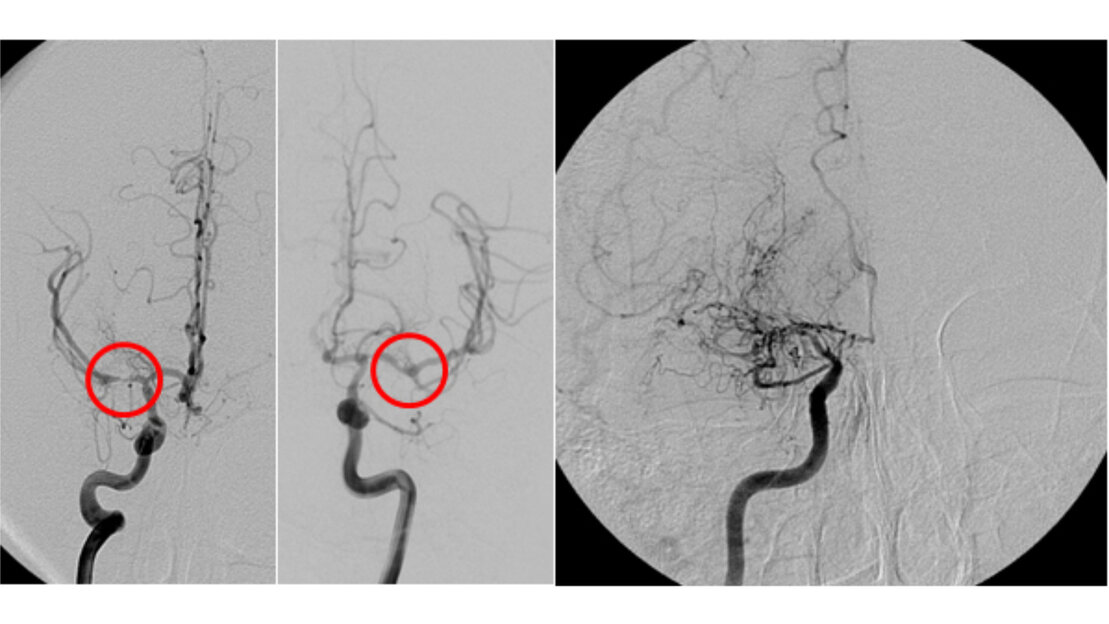

Arterio-venöse Malformationen (Angiome) stellen ein Gefäßknäuel aus krankhaft veränderten Gefäßen dar, die zu einem Kurzschluss zwischen Arterien und Venen führen, ohne dass ein dazwischengeschaltetes Kapillarbett gebildet wird. Hierdurch kann es zur Minderdurchblutung des umliegenden Hirngewebes kommen, was sich auch in epileptischen Anfällen äußern kann. Die Gefäße des Knäuels (Nidus) neigen aber auch zu Einrissen der Gefäßwand mit der Folge einer Blutung in das Hirngewebe. Die Entdeckung eines Angioms erfordert daher eine Behandlung. In unserem Zentrum wird meist ein interdisziplinäres Behandlungskonzept erstellt, bei dem zunächst ein größtmöglicher interventioneller Verschluss (Embolisation) des Nidus angestrebt wird mit sich anschließender operativer Entfernung des Befundes. Eine unvollständige Ausschaltung eines Angioms führt häufig zum Wiederauftreten des Befundes, was dieses aufwändige Behandlungsverfahren begründet. Eine weitere, zur Verfügung stehende Option ist die Bestrahlung, die allerdings erst mit mehrjähriger Verzögerung einen Effekt auf das Angiom hat. In einer großen Metaanalyse1, in der insgesamt 13.698 Patienten ausgewertet worden sind, zeigte sich ein erfolgreiches Ausschalten der AVM in 96% der Fälle (range 0 %-100%) nach mikrochirurgischer OP, in 38 % der Fälle (range 0 %-75 %) nach stereotaktischer Bestrahlung und in 13 % der Fälle (range 0 %-94 %) nach Embolisation.

AV-Fisteln sind direkte Kurzschlüsse zwischen Arterie und Vene ohne jegliche zwischengeschaltete Gefäße. Sie liegen häufig im Bereich der harten Hirnhaut (Dura) vor und sind mit einem erhöhten Risiko einer Hirnblutung verbunden. Die primäre Behandlungsform besteht im interventionellen Verschluss, welcher von den Neuroradiologen durchgeführt wird. Falls dieser nicht oder nur unvollständig gelingt, ist eine operative Beseitigung der Fistel erforderlich und in unserer Klinik auch möglich.